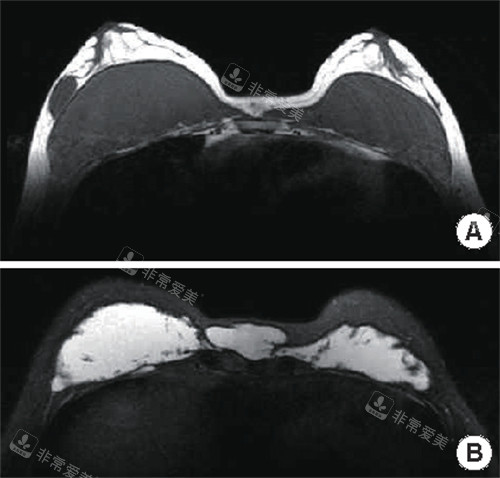

奥美定取出改善